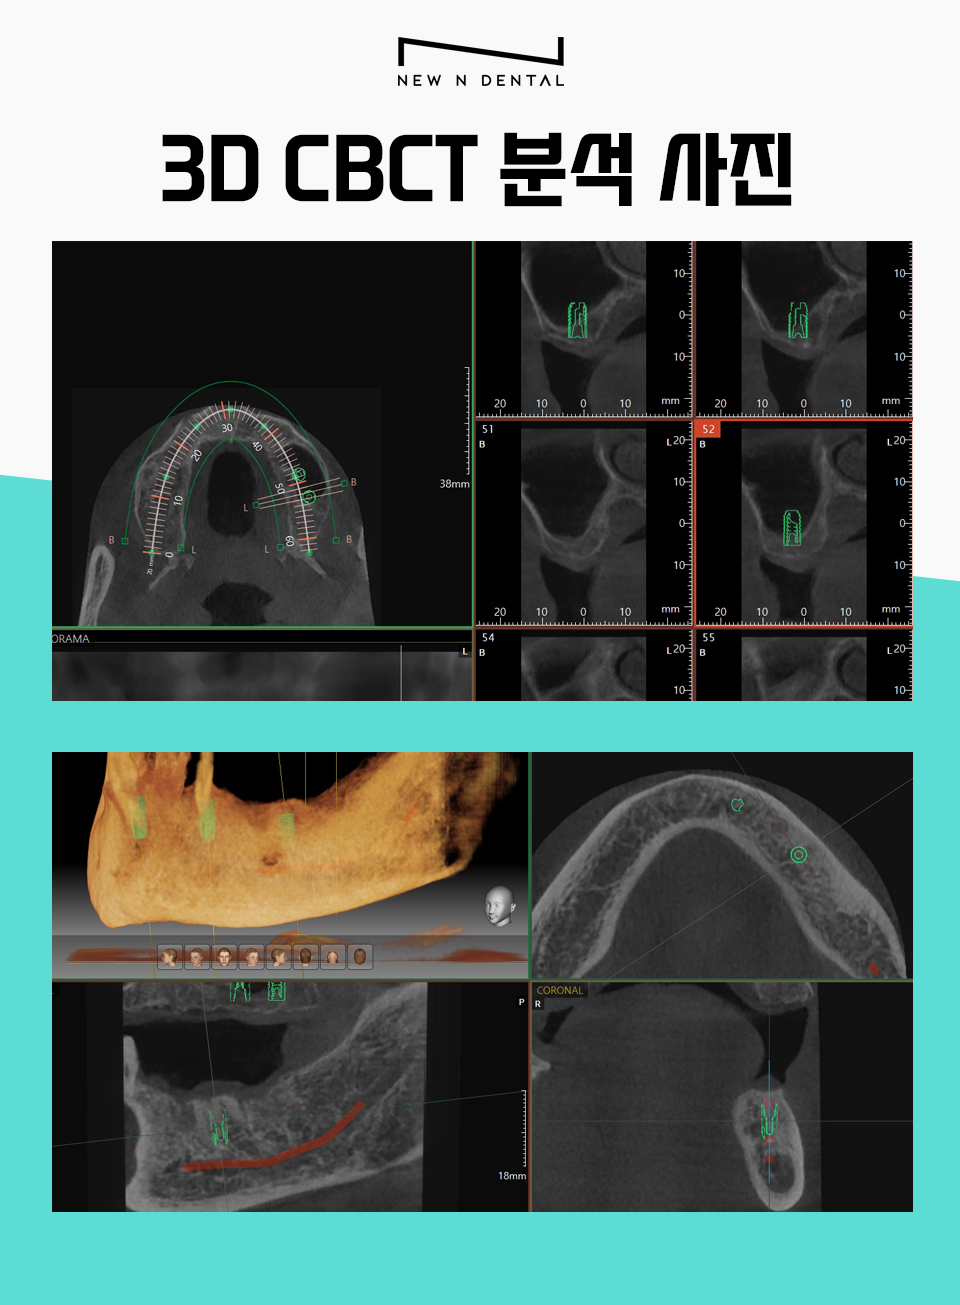

현재 상태를 파악하기 위해서

우선 3D CT와 x-ray를 통해서

구강 구조물과 상태를 확인하는 과정을 거쳤습니다.

CT와 X-ray를 통해서 상악 구치부에 있는

잔존 치조골의 높이와

필요한 뼈이식의 양을 먼저 파악했습니다.

또한 하치조 신경관의 위치를 3D CT로 분석해서

인공치아가 식립 될 수 있도록

전체적인 치료계획을 수립했습니다.

하악 CT의 경우 하치조 신경(붉은색 처리된 부분)과의

거리를 분석하여 신경손상이 거의 없도록

미리 예측하고 식립 합니다.